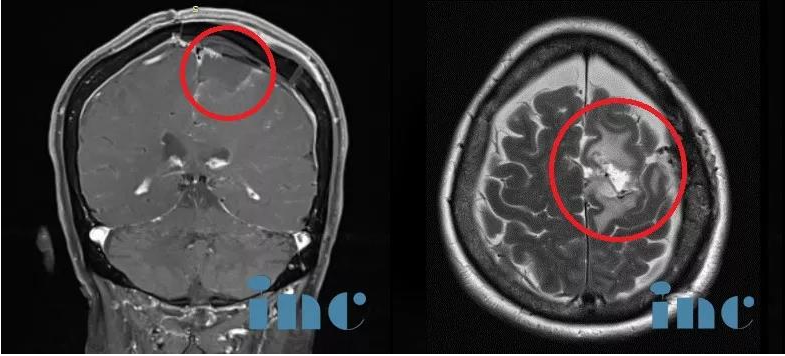

術(shù)前MR——較大腦膜瘤手術(shù)

巨大腦膜瘤手術(shù)案例——術(shù)前MR

腦膜瘤鈣化和瘤周壓迫、水腫效應(yīng)明顯,且已侵襲矢狀竇,壓迫運(yùn)動(dòng)功能區(qū)